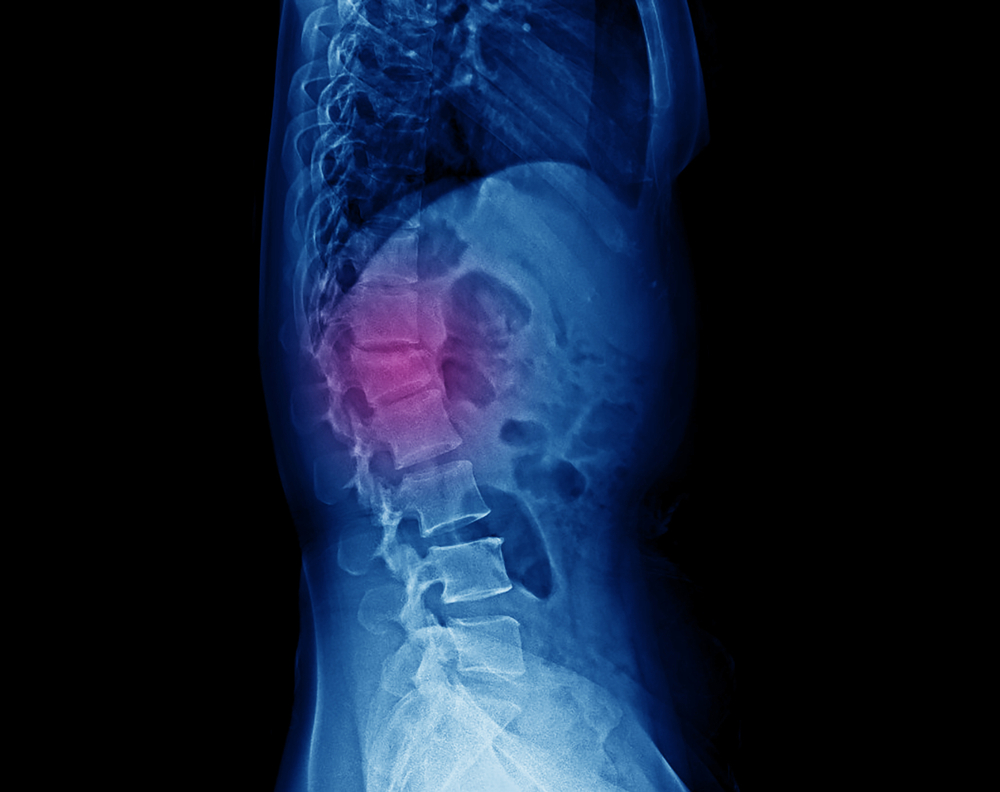

The spine is made up of vertebrae separated by discs that act as shock absorbers.

When these discs become compressed due to injury or wear and tear, it can result in

pain, numbness, or weakness in the back and legs.

Spinal decompression works

by gently stretching the spine. This change in force and position of the spine takes

pressure off the spinal discs, in particular bulging or herniated discs, by creating

negative pressure in the disc. As a result, the disc is pulled back into position,

and the flow of nutrients and other substances necessary for healing is facilitated.